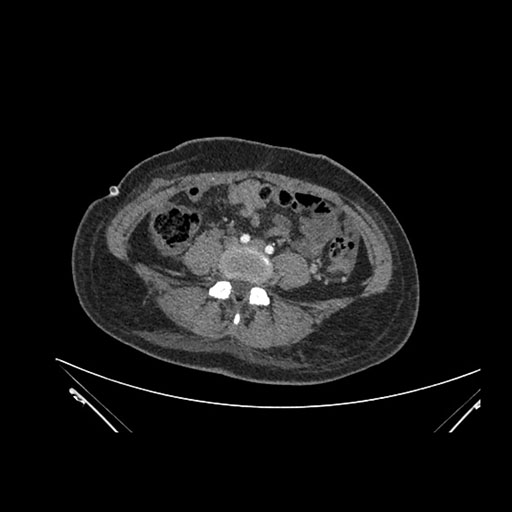

Imaging Analysis

Look through the patient's CT scan to identify any areas of concern for the necessary procedure.

Axial Arterial

Based on initial findings, which issue(s) would you be most concerned about?